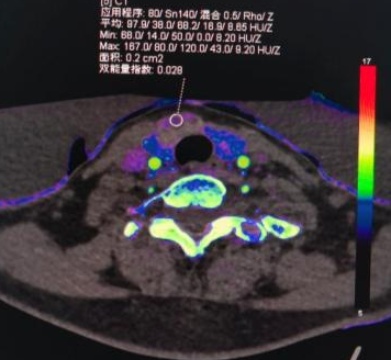

(a) (b) (c) (d)

(e) (f) (g) (h)

(e)~(h)结节性甲状腺肿患者双能量CT增强扫描动脉期原始图像、碘图、Rho/Z图及病理图

Figure 1. Examples of dual-energy CT arterial phase images, iodine uptake images, Rho/Z images, and pathological findings in three groups of patients with thyroid nodules (HE, ×100, H) (Rho/Z, Electron Density/Effective Atomic Number)

1. 三组甲状腺结节患者双能量CT动脉期图、碘图、Rho/Z图及病理图示例(HE, ×100, H) (Rho/Z,电子密度云/有效原子序数)